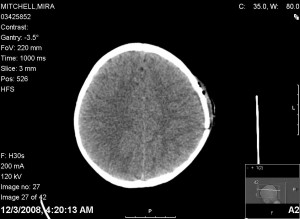

4AM we got the wake up call for the cat scan. Mira was remarkable calm for this one. The result of the scan looked like this:

Clearly the hematoma is gone. You can still see some of the swelling on the outside, but it looks good inside the skull.